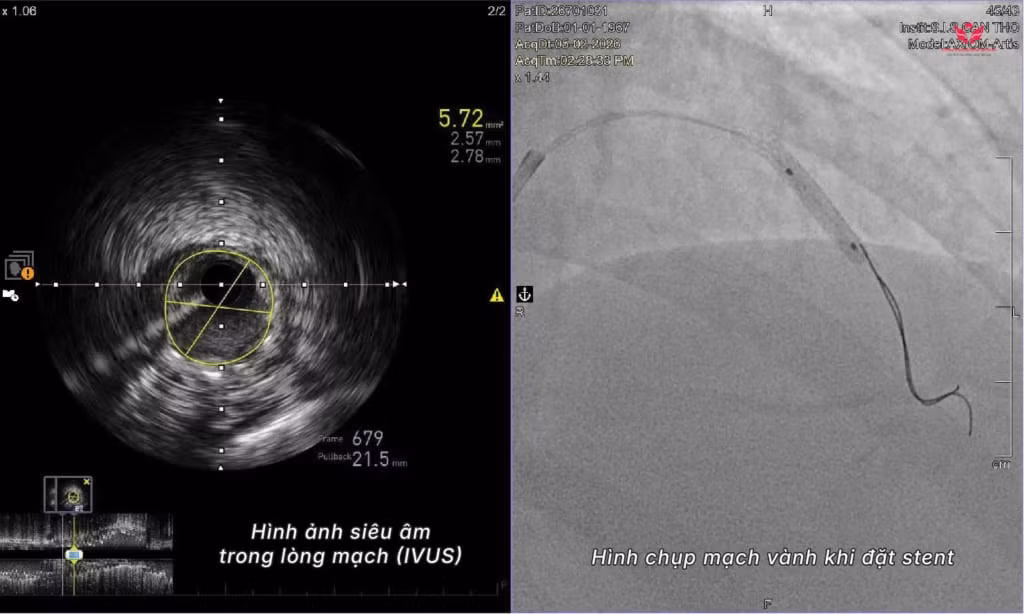

Bác sĩ Chỉnh cho biết: Chúng tôi đã có dữ liệu hình ảnh CT mạch vành trước đó để định hướng các mốc giải phẫu. Trong quá trình can thiệp, thay vì dùng thuốc cản quang, ê-kíp sử dụng siêu âm trong lòng mạch (IVUS) để quan sát trực tiếp bên trong động mạch và tiến hành đặt stent tái thông thành công.

Bác sĩ CKI Nguyễn Đức Chỉnh chia sẻ, để thực hiện can thiệp mạch vành không sử dụng thuốc cản quang, các đơn vị y tế cần đáp ứng hai điều kiện: Bác sĩ cần nắm rõ giải phẫu mạch vành của bệnh nhân từ trước thông qua các dữ liệu hình ảnh, đồng thời đơn vị phải có các thiết bị hình ảnh nội mạch chuyên sâu như siêu âm trong lòng mạch (IVUS) để quan sát trực tiếp lòng và thành động mạch.